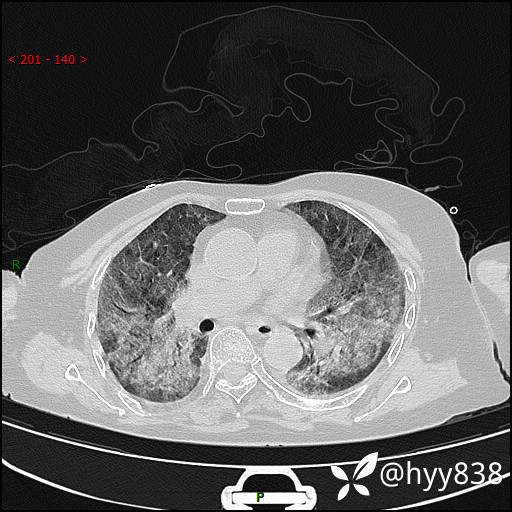

弥漫性肺部病变,辗转当地多家医院未能确诊,拟诊“重症肺炎”入我院--结果公布

患者年龄:69岁

简要病史: 患者20余天前无明显诱因出现发热,最高体温37.5℃,伴头晕,乏力,纳差等不适,无鼻塞,流涕,无咳嗽咳痰,无呼吸困难,无恶心呕吐、关节疼痛等不适,于当地市多家医院就诊,未明确病因,2023.6.23于当地第二人民医院就诊,完善胸部CT示病毒性肺炎,予以抗感染、清热解毒后症状较前稍好转,2天前患者无明显诱因出现活动后喘息加重,伴肌肉酸痛,口干,无明显咳嗽咳痰,今日体温38.1℃,为求进一步诊治来我院就诊,门诊以“ 重症肺炎 I型呼吸衰竭”收入院。 患者起病以来,精神、睡眠、饮食欠佳,大小便正常,体力下降,体重无明显改变。

辅助检查:CT

临床诊断:重症肺炎

胸部CT薄层扫描